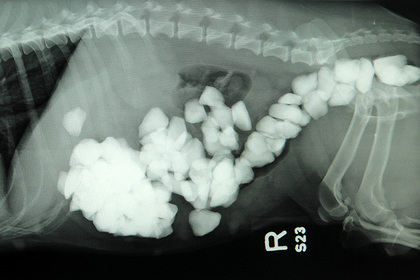

图自台媒中新网8月26日电据台湾媒体报道,英国兰开夏郡一头杰克罗素梗犬,平常都在主人家扑满碎石子的后院玩,日前主人发现小狗精神很差、食欲不振,带它去看兽医。

兽医判断小狗腹内有异物,照了X光后大吃一惊,原来小狗的肠道内已经塞满了大大小小的石头,经过紧急手术将石头取出,竟有80多颗。

兽医表示,如果不马上处理,小狗的肠道可能破裂。现在小狗已经恢复健康。